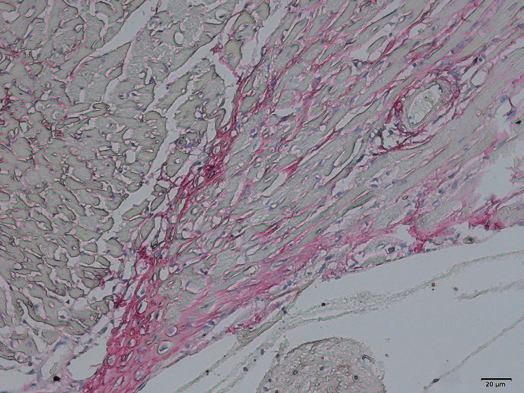

一、病理常规染色及特染项目

天狼星染色vs股骨病理分析

肿瘤病理分析VS心脏组织Masson染色

病理常规染色及特染项目